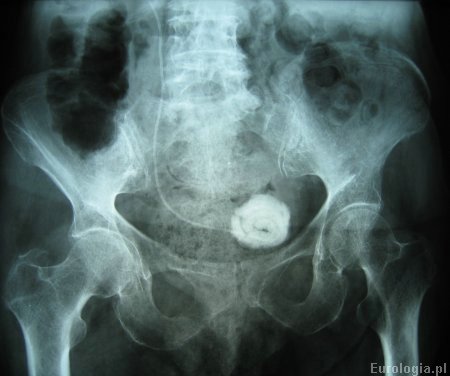

Fot. Kalcyfikacja cewnika DJ - złóg średnicy 5 cm na końcu pęcherzowym cewnika.

Fot. Zdjęcie końca pećherzowego cewnika DJ w powiększeniu.